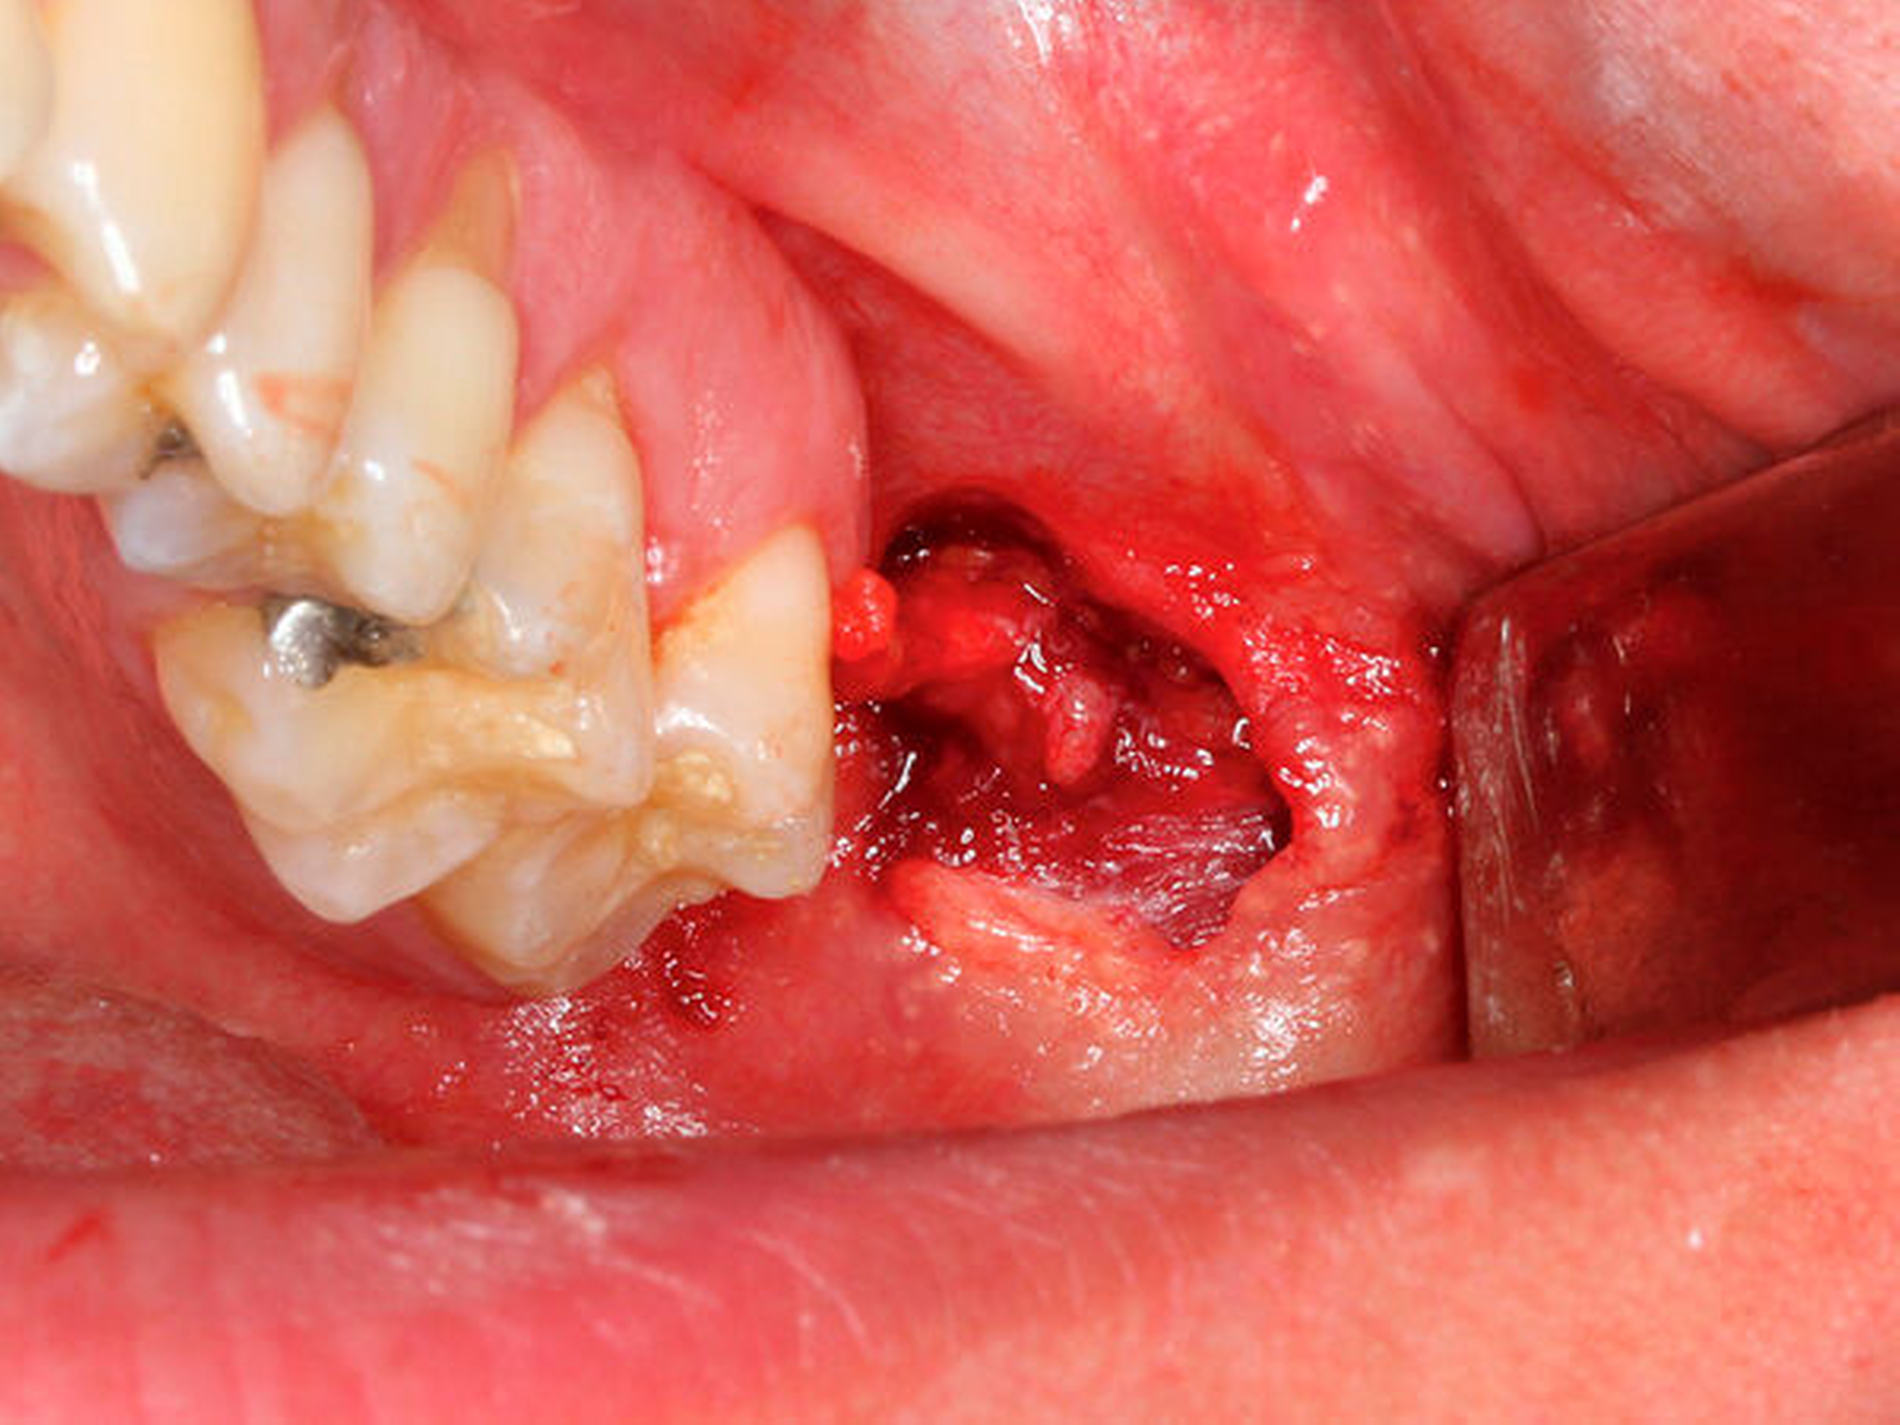

Zusammen mit dem Patienten wurde der Entschluss zur operativen Exploration gefällt. Aufgrund der in der DVT vermuteten Nähe zur Mundhöhle erfolgte dies von intraoral über einen Zugang im Bereich des linken aufsteigendes Astes (Abbildung 2). In Lokalanästhesie konnte der sich nun als Geschoss (Spitzkopfdiabolo, Kaliber 4,5 mm) offenbarende Fremdkörper (Abbildung 3) nach vorsichtiger Präparation in die Tiefe mit der zahnärztlichen Pinzette lokalisiert und geborgen werden. Der postoperative Wundschmerz klang wie erwartet innerhalb einiger Tage ab. Wider Erwarten kam es jedoch zu einer nur marginalen Verbesserung der initial beschriebenen Symptomatik, da sich im späteren Verlauf zunehmend Hinweise auf eine CMD fanden.